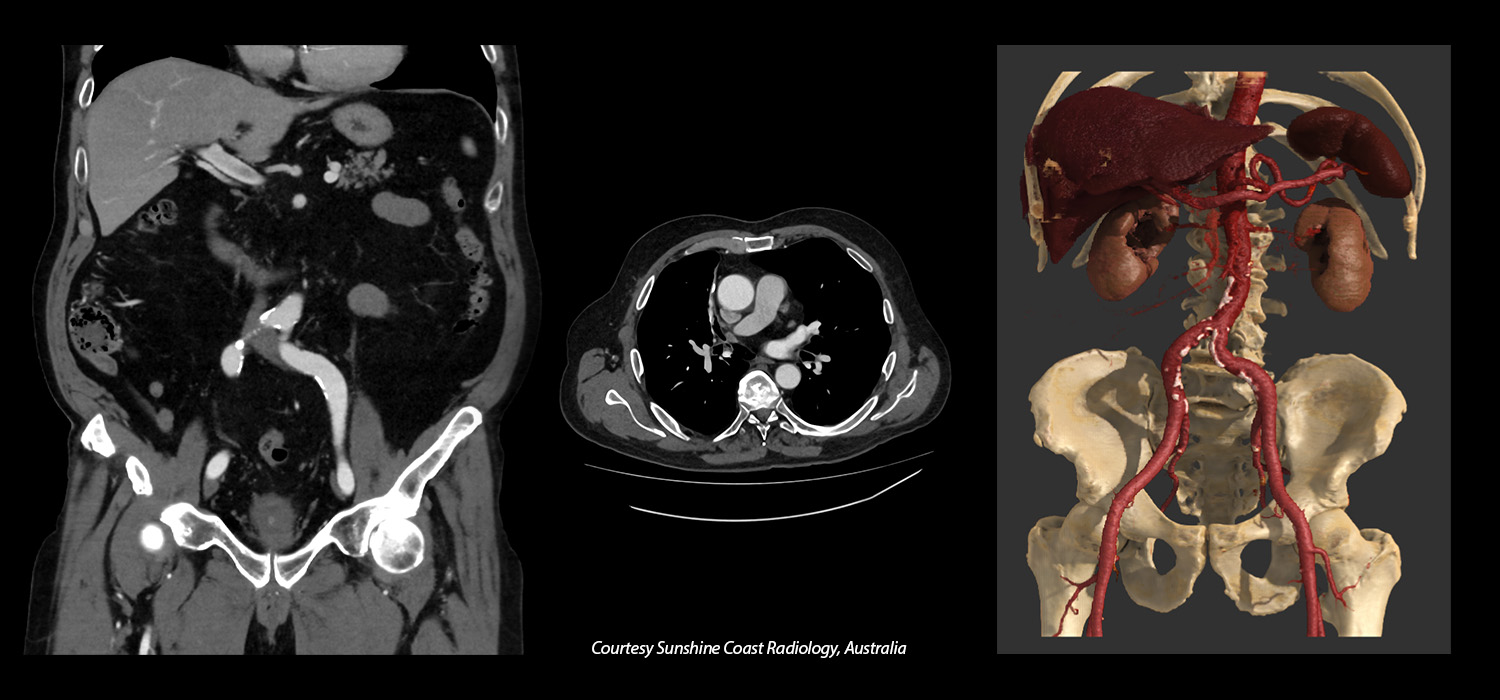

73 BPM Helical Gated Coronary Evaluation

Aquilion Serve SP

Coronary analysis on the Aquilion Serve SP with excellent temporal resolution and AI-power reconstruction with Advanced intelligent Clear-IQ Engine (AiCE) Deep Learning Reconstruction for sharp, clear, and distinct images improves consistency and diagnostic confidence.

View Scan Parameters| Scan Mode | kVp | mAs | Reconstruction | CTDIvol | DLP | Effective Dose† |

|---|---|---|---|---|---|---|

| Gated Helical | 135 | SUREExposure | AiCE | 65.7 mGy | 980.3 mGy·cm | 13.7 mSv |

† AAPM Report 96, k-factor 0.014

* Option

1 Global Illumination is a purchasable option, available in combination Vitrea® Advanced Visualization